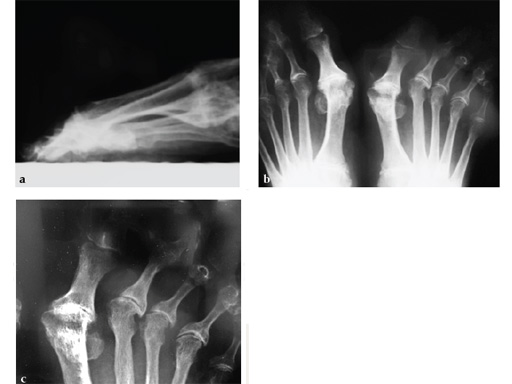

Case 1: First MP fusion VA-LCP

A 57-year-old woman has suffered rheumatoid arthritis for several years. She presented with pain and deformity in the left forefoot moreso than in the right. Clinical examination reveals severe hallux valgus deformity and dislocation of MP joints 11 through V, with synovitis.

Case provided by Juan Bernardo Gerstner, Cali, Columbia

A dorsal transtendinous approach was used and reaming of the first MT head and basal articular surface of the proximal phalanx was performed with the new reamers (see Fig. 3a-b).

A left MP fusion was performed as well as a II to V MT head resection arthroplasty, and fixed with K-wires for 4 weeks (see Fig. 4a-b). The patient was weight bearing immediately with wooden shoes and K-wires were removed 4 weeks postoperatively.